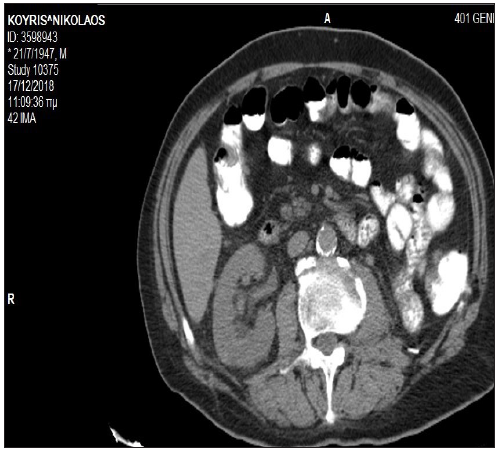

A 69 years-old male, smoker, with a past history of hypertension, depression, benign prostatic hyperplasia, and hypercholesterolemia, presented with macroscopic hematuria and weight loss. Computed tomography scans revealed a left renal mass, bilateral pulmonary nodules, and thickening of the hepatic flexure colon mass. Patient underwent a left nephrectomy and the histopathological examination confirmed the presence of a grade 3, pT3Nx, clear-cell carcinoma. Colonoscopy identified a mass in the transverse colon covering three quarters of the lumen and the histological report confirmed the presence of a moderately differentiated invasive colon adenocarcinoma (Figure 1). Post surgery CT scans revealed deterioration of the known pulmonary lesions and presence of a new left pleural effusion (Figure 2a) together with a hepatic flexure colon mass (Figure 2b). A CT-guided lung lesion biopsy was consistent with RCC metastatic disease. In view of the asymptomatic colon cancer and the rapidly imaging deterioration of the metastatic renal cancer, treatment with pazopanib commenced with acceptable toxicity and partial response of both the renal metastatic disease and the colonic primary tumor. After eight months of treatment, imaging tests revealed disease progression in the lung, while the colon mass was further responding. Second-line treatment with axitinib commenced and the restaging CT scans, after 10 months from initial diagnosis, were consistent with a new partial response of metastatic disease (Figure 3a & 3b), while a new colonoscopy revealed complete remission of the colon cancer. Treatment with axitinib continued for 5 months overall, with good tolerance. The patient presented brain and leptomeningeal metastatic disease with rapid clinical deterioration and succumbed 15 months after initial diagnosis.

Figure 3b: An abdomen CT scan after 10 months of treatment with TKIs showing normal appearance of the transverse colon.